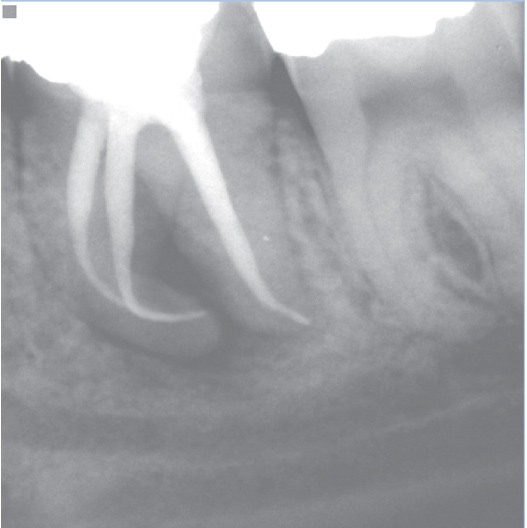

After

After Root Canal treatment